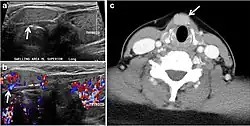

- Fig. 7. A 51-year-old female patient post total thyroidectomy for PTC with elevated thyroglobulin measurement. an Axial non-enhanced CT scan of the neck at the level of the thyroid bed demonstrates a well-defined, rounded, homogenously dense soft tissue situated between the trachea and left internal jugular vein (white arrow). b Transverse ultrasound image of the neck demonstrates a well-defined, homogeneous, hypoechoic soft tissue nodule measuring 6 mm (white arrow) with no detected micro-calcifications. Biopsy showed a predominantly residual normal thyroid tissue with micro-foci of PTC.[1]

- Fig. 8. A 48-year-old male patient post total thyroidectomy with PTC recurrence. a Transverse greyscale ultrasound of the neck demonstrates a left thyroid bed heterogeneous, predominantly hypoechoic irregular lesion with calcifications (white arrow). b A spot image of iodine 123 total body scan of the neck demonstrate a focus of abnormal radiotracer uptake at the left thyroid bed (Black arrows) between the annotated markers. c Enhanced axial CT scan of the neck demonstrates an enhancing large left thyroid bed mass (white arrow) with no calcifications. The lesion exerts a mass effect on the oesophagus (black arrow) and is inseparable from the trachea.[1]

- Fig. 9. A 58-year-old male patient with persistence PTC at thyroid bed with hypervascular nodal metastasis. a–c Transverse greyscale and colour Doppler neck ultrasound demonstrate hypoehoic soft tissue in the left thyroid bed (white arrow in a). There are a heterogeneous enlarged lymph nodes at level 2 and 3 with markedly increased vascularity (white arrow in b and c). d–f Enhanced axial CT images of the neck demonstrate a 2.7 × 1.4 cm hypodense soft tissue lesion anterior to the left carotid sheath (white arrow). There are left-sided enhancing abnormal and enlarged lymph nodes at cervical level 2 and 3 (black arrows).[1]